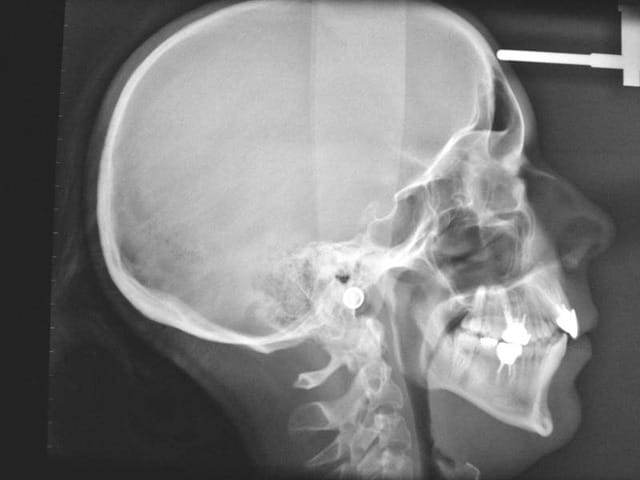

Voici les Rx. de début

notre ami Zorglub pourra ainsi nous faire part de

ses objectifs de TTT.

son plan de TTT.

et les justifier

Rx - Eugenol